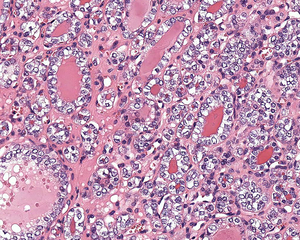

كبسولة ورم الغدة الدرقية NIFTP

لا يوجد دليل على غزو كبسولة النسيج الضام الليفي جيدة التكوين ، مما يساعد على دعم تشخيص NIFTP.

يُظهر ورم NIFTP سمات نووية محددة لسرطان الغدة الدرقية الحليمي.

السمات النووية لسرطان الغدة الدرقية الحليمي ، ولكن داخل ورم مغلف: NIFTP

1) مغلفة أو مغلفة جزئيا. عادة ما تكون الأورام محددة جيدًا أو محوطة ، مع تغليف أغلبيتها ، ومحاطة بكبسولة نسيج ضام ليفية جيدة التكوين.